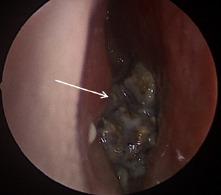

Unilateral nasal obstruction is a common complaint with a broad differential diagnosis that includes anatomic asymmetry, unilateral infective or inflammatory conditions, and benign and malignant sinonasal masses. A rhinolith is an uncommon foreign body in the nose, which serves as a nidus for calcium salt deposition. The foreign body can be endogenous or exogenous in origin and may remain asymptomatic for many years before incidental discovery. When left untreated, stones may cause unilateral nasal obstruction, rhinorrhea, nasal discharge, epistaxis or, in rare cases, progressive destruction leading to septal/palatal perforation or oro-antral fistula. Surgical removal is an effective intervention with limited complications reported.

This article describes a 34-year-old male who presented to the emergency department (ED) with unilateral obstructing nasal mass and epistaxis, which was found to be an iatrogenic rhinolith. Successful surgical removal was performed.

Epistaxis and nasal obstruction are common presentations to the ED. Rhinolith is an uncommon clinical etiology that if left undiagnosed may lead to progressive destructive disease; it should be included in the differential for any unilateral nasal symptoms of unclear origin. Appropriate work-up for any suspected rhinolith includes computed tomography, as biopsy is risky given the broad differential of unilateral nasal mass. When identified, surgical removal has a high success rate with limited complications reported.